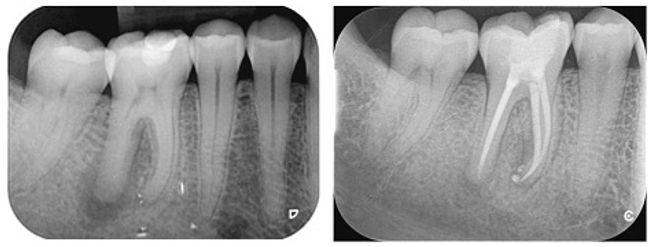

The length of the root canals is then determined using an X-ray.

On a final X-ray, the dentist can check whether the filling material fills the lumen as it should.

A filling is then made and after about 3 months we can check on an X-ray whether the result is as we expected. See x-rays at top.